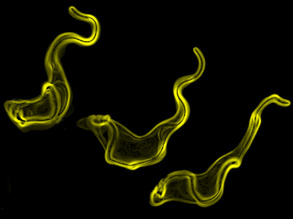

Worm Therapy?

09